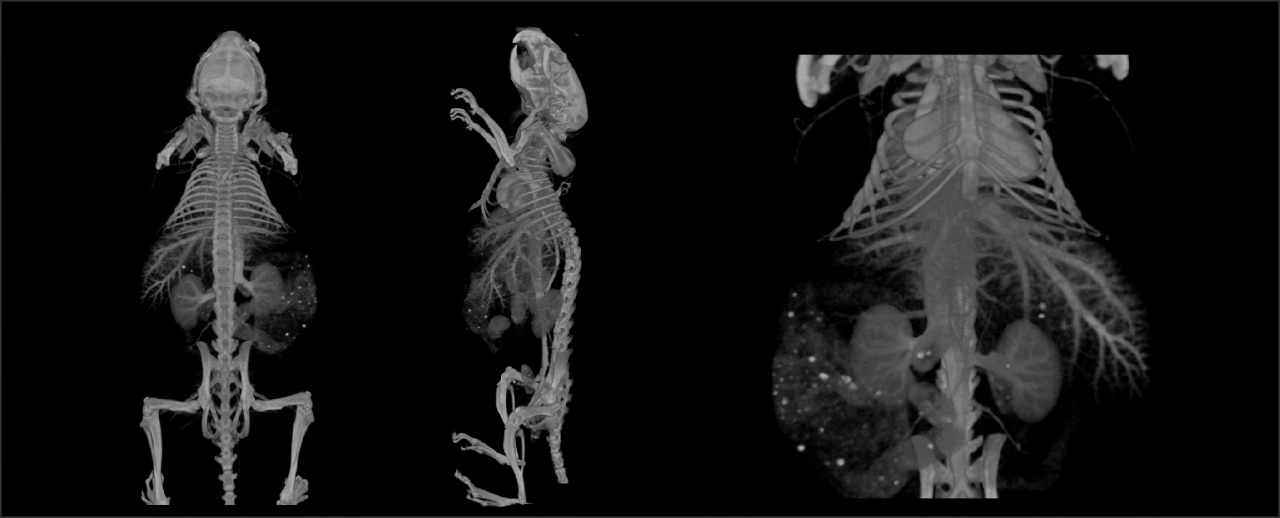

The PET/CT Si78 is a high throughput imaging instrument, dedicated for drug and tracer development for clinical translation . It combines highest PET sensitivity with fast and low dose CT.

The PET/CT Si78 is a molecular imaging system for sequential Positron Emission Tomography (PET) and X-Ray Microtomography (uCT). The fully shielded scanner, the animal welfare solutions and the experimental workflows are designed to support high throughput translational preclinical research in all field s of nuclear molecular imaging research.

• Up to 0.7 mm spatial resolution

• Up to 12 % sensitivity

• 150 x 80 mm FOV

• True DOI, no loss of resolution across FOV

• 52 µm resolution

• 80 (200) x 80 mm FOV single (multiple) bed positions